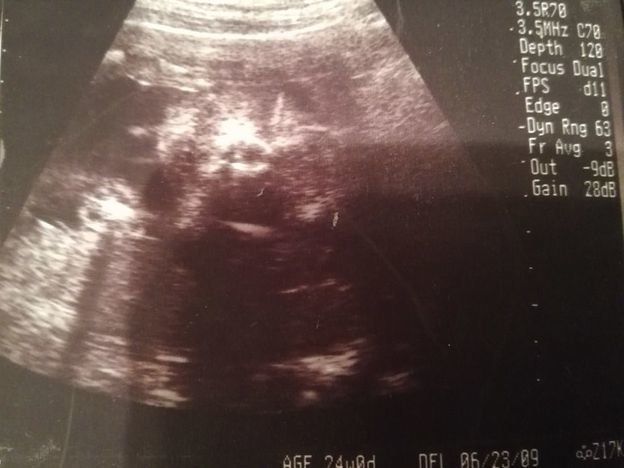

妊娠24週目のエコー写真

前回の妊婦検診から3週間後に出血して、この検診の前に慌てて受診したこともありました。原因は、“逆子”になっていた赤ちゃんに子宮を思い切り蹴られていたため。そんなこともありつつ迎えた、定期の妊婦検診。「出血はなくなりました」と先生に伝えたら、「赤ちゃんも逆子じゃなくなっているよ」と先生。ひとまず“逆子”がなおって良かったと主人にメールしました。